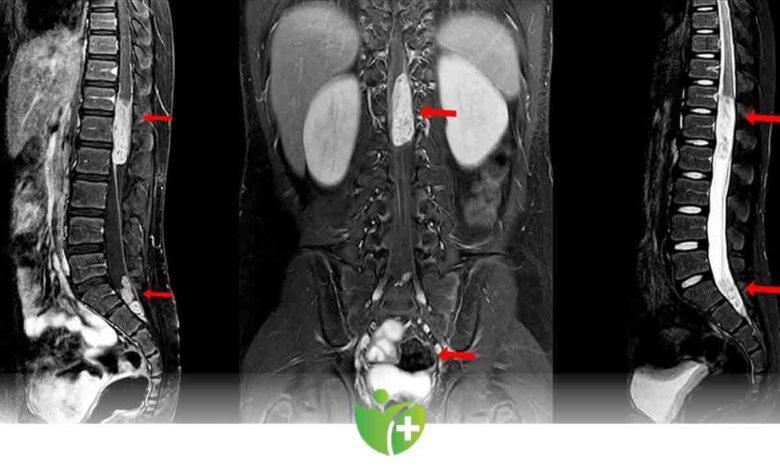

• Manyetik rezonans görüntüleme (MRG). MRG, omurga, omurilik ve sinirlerinizin doğru görüntülerini üretmek için güçlü bir mıknatıs ve radyo dalgaları kullanır. MRG genellikle vertebral tümörleri teşhis etmek için tercih edilen testtir. Belli dokular ve yapıları vurgulamaya yardımcı olan bir kontrast madde, test sırasında ayağınızdaki veya önkoldaki bir damar içine enjekte edilebilir.

• Bilgisayarlı tomografi (BT) taraması. MRG yumuşak dokuları daha ayrıntılı gösterirken BT kemik yapıları göstermede daha üstün ve kullanışlıdır. BT taraması MRG ile kombinasyon halinde kullanılabilir. Ayrıca nereden kaynaklandığı bilinmeyen metastaz hastalarında primer odağı saptamak için akciğer, karın (batın) tomografisi çekilir.

Metastatik hastalarda başka bir omurga lokalizasyonunda da lezyon olabilme ihtimalinden dolayı (%15) görüntüleme yöntemleri tüm omurgayı içerecek şekilde çekilmelidir.